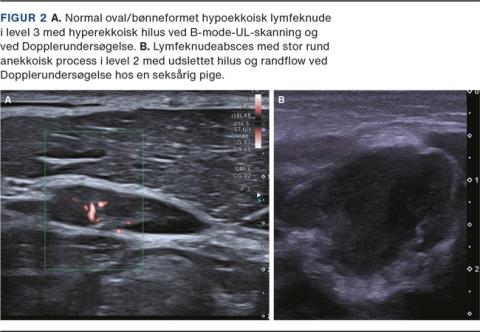

SPYTKIRTLER

De store spytkirtler udgøres af gl. parotidea, gl. submandibularis og gl. sublingualis og ses som homogene og let hyperekkoiske strukturer sammenlignet med den omkringliggende muskulatur (Figur 3). UL-skanning bruges oftest som led i diagnostikken af palpapel spytkirteltumor eller ved mistanke om spytsten/absces. Pleomorft adenom er en benign tumor, som kan findes i alle spytkirtler og kan undergå malign transformation. Små tumorer ses som en homogen, solid, hypoekkoisk proces med posteriort enhancement og perifer vaskularisering [15] (Figur 3). Store tumorer kan være mere heterogene og have en diffus afgrænsning til det omkringliggende spytkirtelvæv. Warthins tumor udspringer fra lymfoidt væv i gl. parotis [16] og ses som en hypoekkoisk proces med heterogen cystisk-solid opbygning. Mindre tumorer er udelukkende solide og kan ved Dopplerundersøgelse forveksles med lymfeknuder med samme hilusflow [17]. Man bør få mistanke om malign spytkirteltumor ved manglende afgrænsning af tumoren, øget heterogent udseende og eventuel nekrose. Vær opmærksom på, at der ikke findes lymfeknuder i gl. submandibularis, så en tumor i denne lokalisation bør altid vække mistanke om malignitet.

Ved akut parotitis er spytkirtlen unilateral eller bilateral diffus forstørret og inflammeret med eventuelt fund af spytsten/dilaterede spytgange eller absces, afhængig af årsagen til inflammationen [18]. Samme fund kan ses ved sialoadentitis, der oftest afficerer gl. submandibularis ensidigt [19]. Ved Sjøgrens syndrom er der ofte bilateralt involvering af gl. parotis ± involvering af gl. submandibularis med heterogent diffust forstørret parenkym med øget Doppleraktivitet og hypo-/anekkoiske områder indlejret [20].